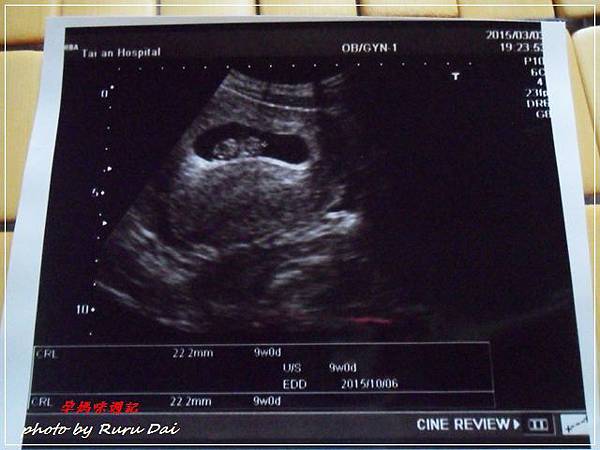

• [孕媽咪週記 8~12週] 正式第一次產檢│終於拿到媽媽手冊│血液常規檢查│出車禍│SMA│FXS│唐氏症篩檢

9週

終於來到了第一次正式產檢的時刻囉!!

真是令人緊張啊~

是說魯魯沒有孕吐,也沒有什麼不適,頂多就是肚子脹脹的熱熱的而已